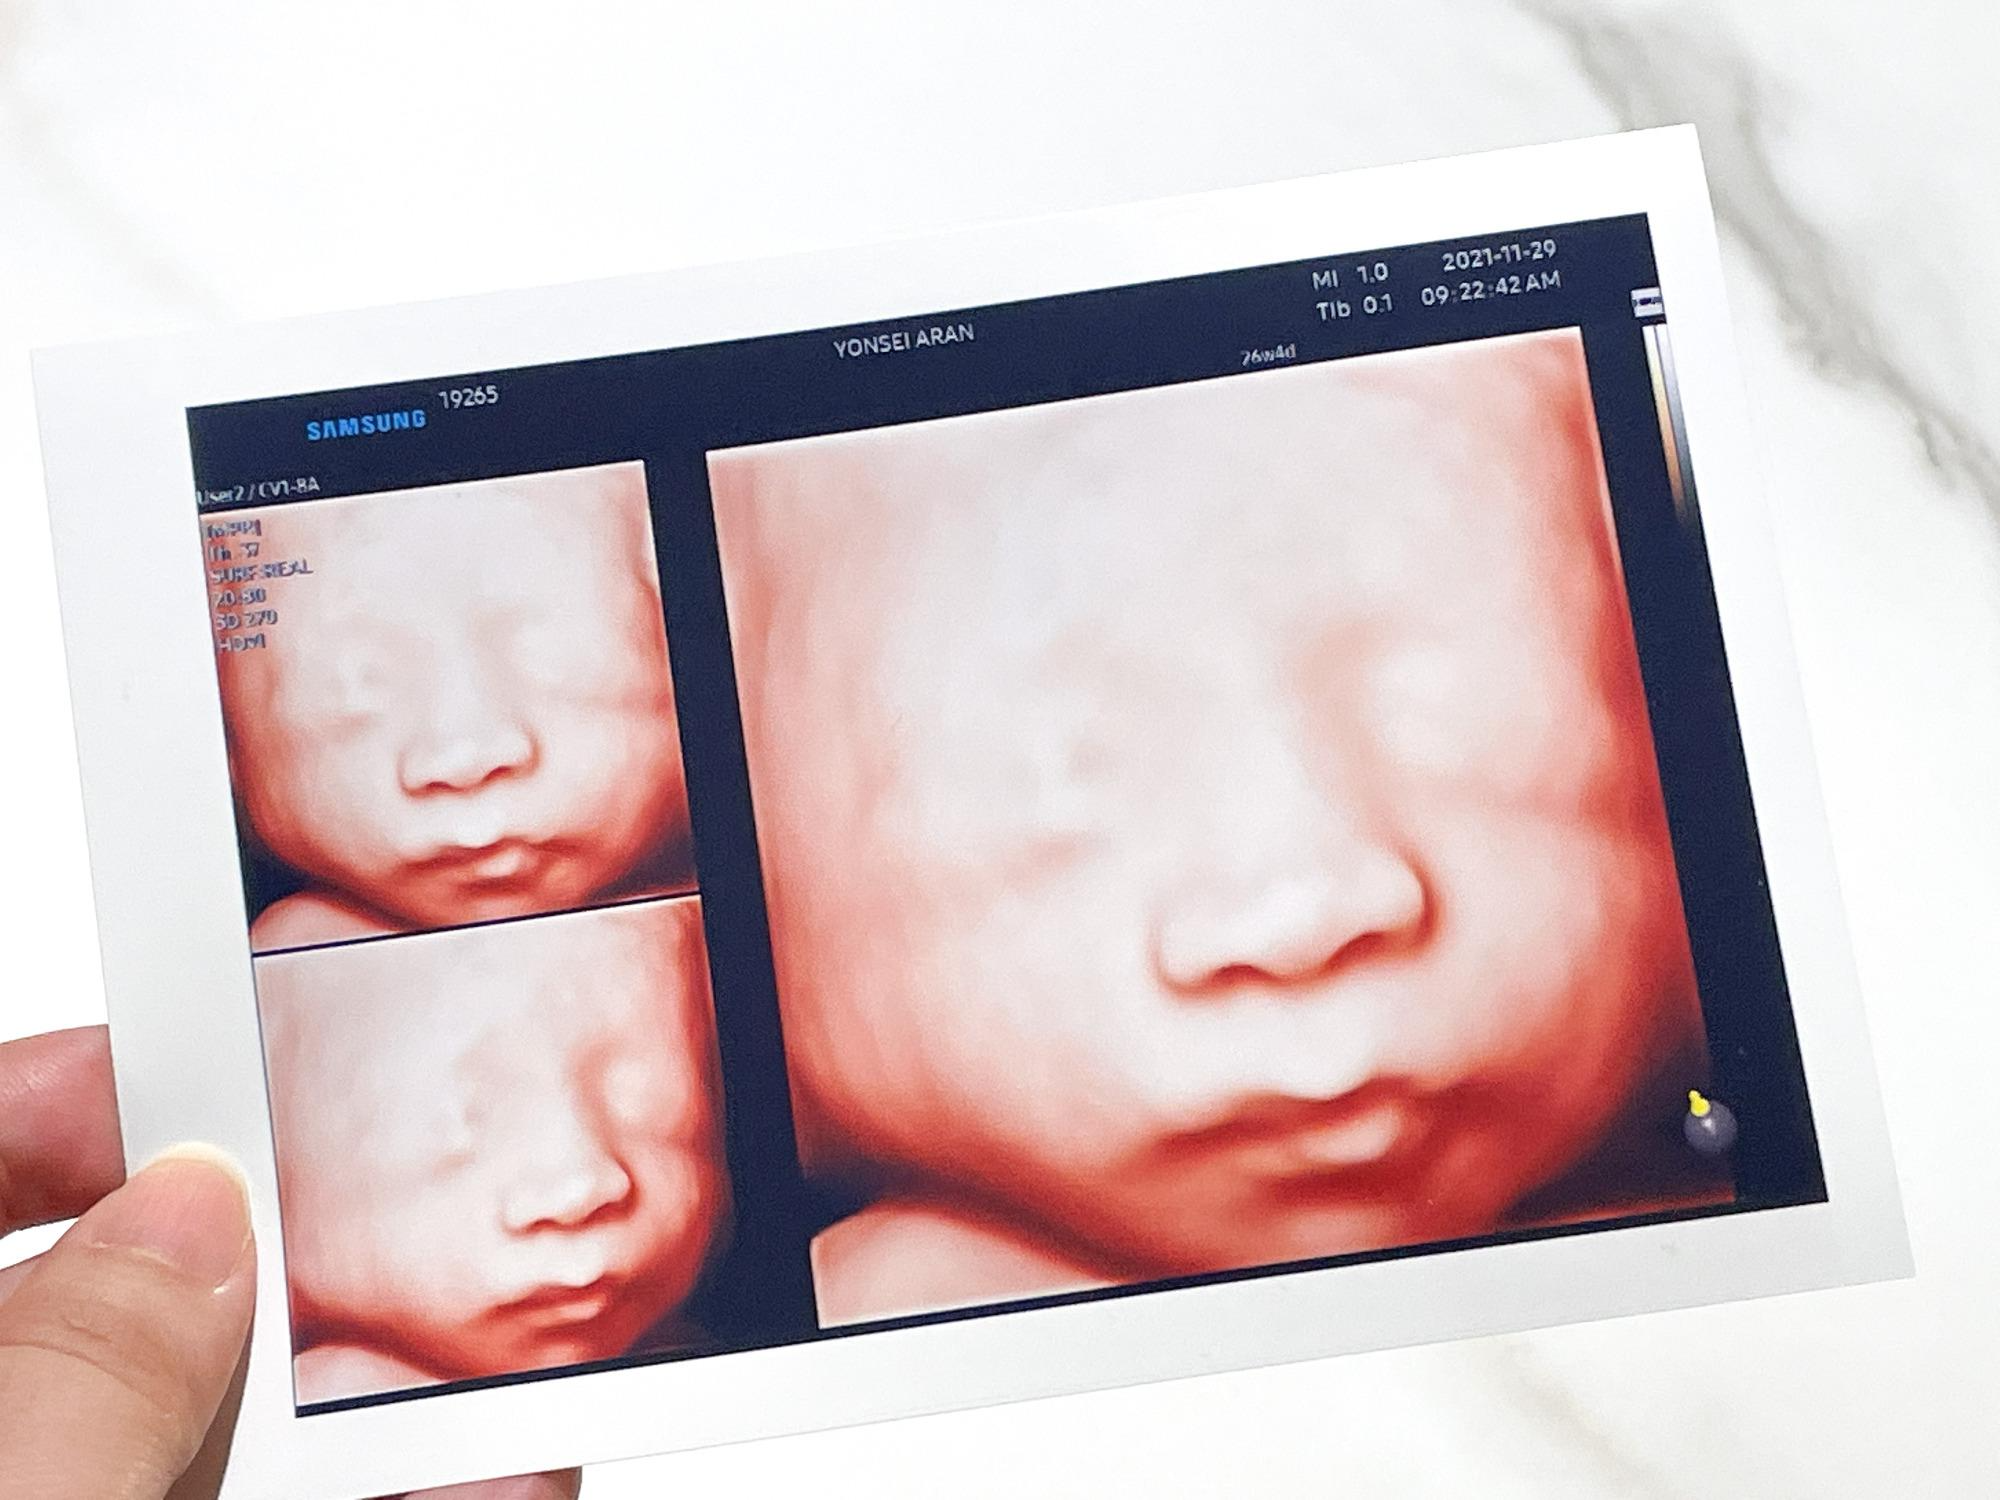

초음파 기기

초음파 사진이 선명하게 잘 나오는 편이었다.

입체 초음파사진도

깔끔하게 이쁜색으로 잘 나왔다.

그리고 애기 초음파 사진도 진짜 이쁘게 여러장 찍어주신다.

덕분에 내 태교 다이어리는 초음파 사진들로 풍년이다ㅎㅎ